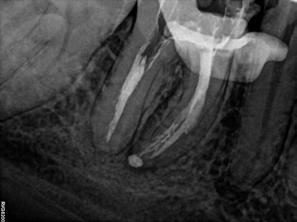

A CBCT-felvételen a fog mindkét gyökércsúcsa körül radiolucens elváltozás volt észlelhető (26. ábra). Ezenfelül a periapikális felvételen a mesiobuccalis gyökérben egy betört eszközt is felfedeztünk (27. ábra).

A pácienst azért irányították a rendelőnkbe, hogy a protetikai kezelések megkezdése előtt három fogát revideáljuk. Ezek közül az egyik egy jobb alsó első nagyőrlőfog volt.

behelyezett guttapercha poénokat az összes csatornából eltávolítottuk (30. ábra). A gyökércsatornák és a fogbélkamra megtisztítása során megállapítottuk, hogy a mesiobuccalis gyökércsatorna bemenete körül korábban jelentős mennyiségű dentint távolítottak el (31. ábra). Ezt valószínűleg a betört eszköz eltávolítására tett kísérletek során végezték el. Szerencsére nem észleltünk perforációra utaló jeleket az adott területen.